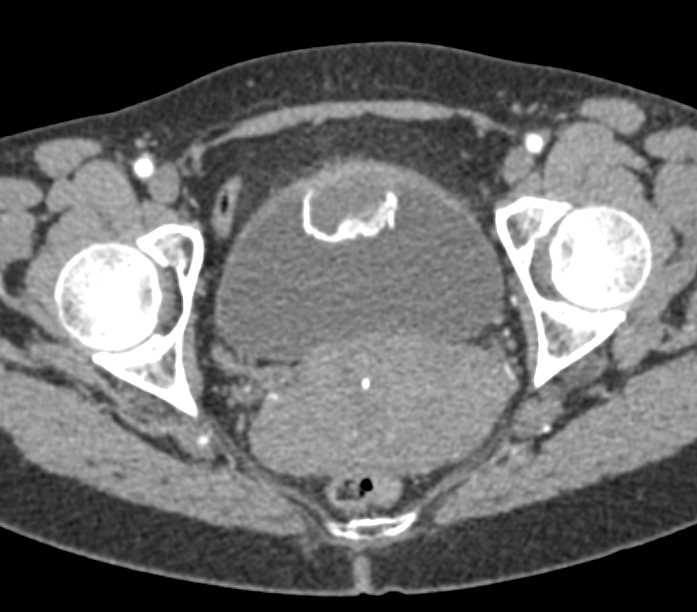

Urachal Carcinoma of the Bladder